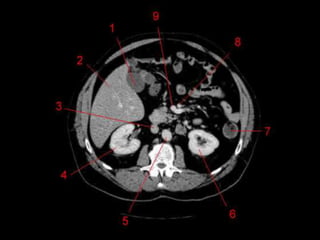

Técnicas de Imagem

• US: Primeiro exame pedido ao: 1) dor no

hipocondrio direito; 2) testes de função

hepáticas anormais; 3) suspeita de

malignidade.

• TC: Tres fases

– Arterial (10 a 20 segundos)

– Fase venosa portal ( 30 segundos )

– Fase venosa hepática (60 segundos)

• TC Portografia: Metastases.

Técnicas de Imagem •US: Primeiro exame pedido ao: 1) dor no hipocondrio direito; 2) testes de função hepáticas anormais; 3) suspeita de malignidade. • TC: Tres fases – Arterial (10 a 20 segundos) – Fase venosa portal ( 30 segundos ) – Fase venosa hepática (60 segundos) • TC Portografia: Metastases.